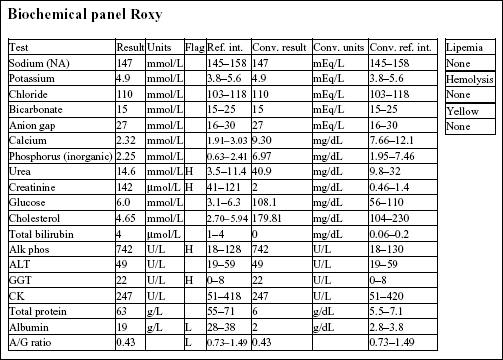

Roxy, a 12.5-year-old F Old English Sheepdog X, had anorexia for 5 days. She had been polydipsic, but was no longer drinking at presentation.

There is a mild to moderate anemia with minimal regeneration. Although the reticulocyte count is 2.2%, the RPI is not increased (>1 indicates regeneration; >3 indicates strong regeneration) and there is no polychromasia noted on RBC morphology. Also, the absolute reticulocyte count is 2.2% × 4.41 × 1012/L = 0.097 × 1012/L, which is only slightly above the reference interval for a normal, nonanemic dog ((0.055–0.085) × 1012/L). There is a moderate to severe leukocytosis characterized by a moderate neutrophilia with a marked left shift, toxic change, and moderate monocytosis. These leukogram changes indicate severe, chronic inflammation.

There is a mild azotemia that must be interpreted in relation to the hydration status of the dog and the urine SG (not available). Moderate elevations in ALP and γ-glutamyltransferase (GGT) activities could be due to cholestasis, enzyme induction, or both. The hypoalbuminemia and low albumin to globulin (A/G) ratio may relate to albumin’s role as a negative acute phase protein.

• The history and laboratory findings support a diagnosis of pyometra in this dog. The anemia is likely due to chronic disease/inflammation. The leukogram abnormalities are due to the demand for phagocytic cells within the uterus. A marked leukocytosis commonly occurs following ovariohysterectomy when pyometra is present. Granulocytic hyperplasia is established in the bone marrow and neutrophils continue to be released into the peripheral blood for several days after the uterus is removed. Since the neutrophils no longer have a focus of inflammation/infection to migrate into, numbers will increase in the circulation (rebound effect). Band cells will eventually decline first, followed by mature neutrophils. The anemia of chronic disease/inflammation will start to correct with resolution of the inflammatory response.